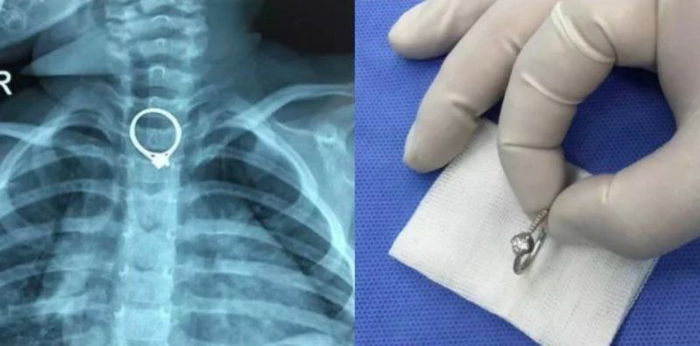

Seorang ibu di Tiongkok berbagi pengalamannya, saat anak menelan benda asing hingga tersangkut di tenggorokannya. Ibu yang tinggal di Provinsi Guangdong di Tiongkok harus merasakan panik saat putri kecilnya yang masih balita menelan cincin berlian miliknya.

Salah satu media melaporkan, balita berusia dua tahun ini merengek minta bermain dengan cincin sang ibu. Ketika ibunya tertidur, si anak mulai menangis sambil menunjuk mulutnya dan mengatakan bahwa dia telah menelan cincin yang ia mainkan.

anak menelan benda asing 1

Anak menelan benda asing hingga tersangkut di tenggorokan.

Sang ibu langsung panik dan segera melarikan anaknya ke Zhuhai Hospital of Integrated Traditional Chinese and Western Medicine. Beruntung, dokter di rumah sakit tersebut berhasil mengeluarkan cincin tersebut dari tenggorokan si anak.

Melalui prosedur operasi yang berlangsung selama 30 menit, cincin berdiameter 2,35 sentimeter itu berhasil dikeluarkan dari tubuh anak. Untungnya kesigapan sang ibu langsung membawa anaknya ke rumah sakit dapat mencegah terjadinya dampak buruk lebih lanjut.